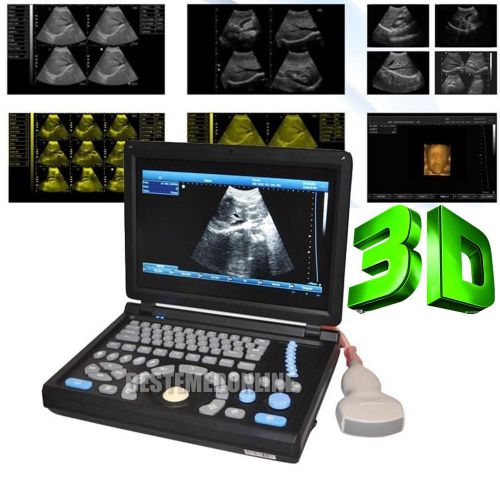

3D PC Platform Full Digital Laptop Ultrasound Scanner+ Convex &Linear BEST CHOIC

HOT HOT HOT! Digital Ultrasound Scanner 4-frequency Convex +Linear probes +3D

3D Digital Ultrasound Scanner +Convex TV 2 probes Optional 2 probes+3 years warr

ONLY 1-MONTH SALE!!! Digital Laptop Ultrasound Scanner Diagnostic + Linear 3D

NEW Full Digital TFT LCD Ultrasound Scanner High-resolution (built-in 3D) CONVEX

FULL DIGITAL Portable Ultrasound Scanner 3 probes "Convex,Linear,TV" +3D GOOD+++

3D Full-digital Ultrasound scanner machine with 3.5MHz R60 convex +2 USB Ports

Hot 3D Full-digital Ultrasound scanner machine W CONVEX +2 connectors+2USB ports

3D 10.1" Full Digital Laptop Ultrasound Scanner Machine +Micro-convex Probe CE

in 3D Full Digital Laptop Ultrasound Scanner (PC) with convex probe Free Ship

NEW 10.4" 3D PC platform Full Digital Laptop Ultrasound Scanner+ 3.5Convex Probe

+Aluminum box Full Digital 3D PC LAPTOP Ultrasound Scanner vaginal NEW